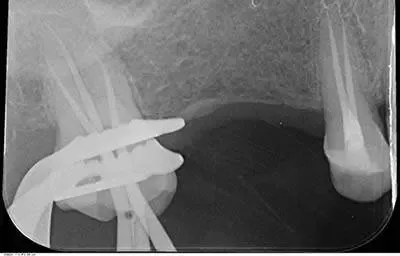

Se il dente è dolente è possibile effettuare un trattamento canalare, definita anche devitalizzazione, un trattamento che rende totalmente asintomatico l’elemento dentale. Successivamente è sempre possibile effettuare una otturazione, ricostruzione o corona.

Anche denti già devitalizzati non curati correttamente e che presentano delle lesioni periapicali (granulomi) si possono recuperare con idonee terapie canalari definiti ritrattamenti dentali.